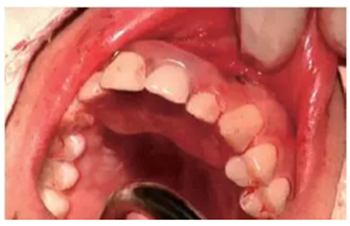

種植完成

種植完成后可以通過拍攝曲面體層或是根尖片來確認(rèn)種植體的植入情況,并作為資料加以保存。

種植手術(shù)完成2周后進(jìn)行拆線??梢钥闯鲕浗M織愈合良好。

圖7 曲面體層片

圖8 拆線時(shí)的口內(nèi)照片